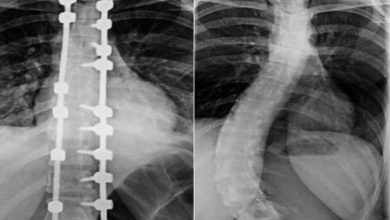

مستشفى الدكتور سليمان الحبيب بالصحافة ينجح في تصحيح ميلان حاد بالعمود الفقري لـ”عشرينية” ويعيدها للحياة الطبيعية

تمكّن فريق طبي في مستشفى الدكتور سليمان الحبيب بالصحافة، من إجراء عملية نوعية ناجحة لتقويم تشوّه متطور بالعمود الفقري لشابة…